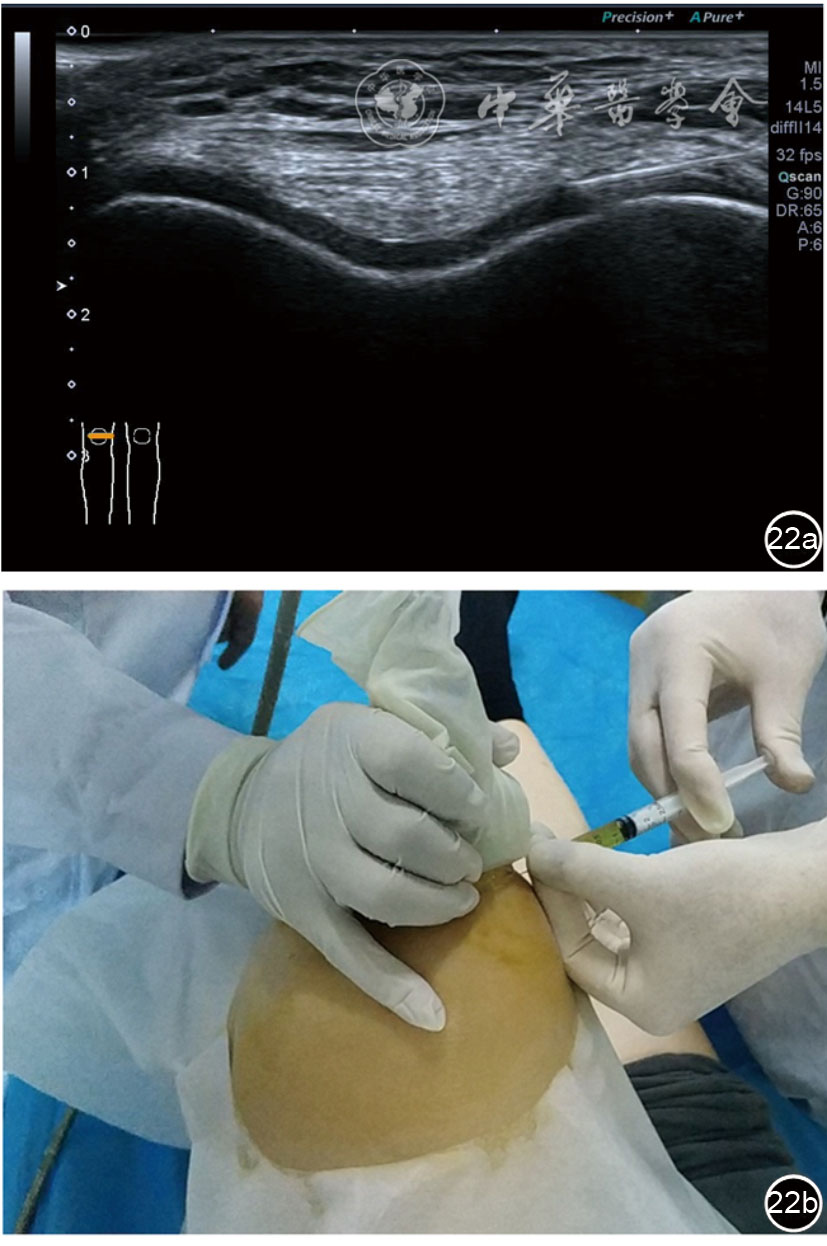

3.膝关节内局部治疗。随着病情发展,静态结构失衡,膝关节内部结构发生变化,会出现软骨损伤、脱落,关节间隙变窄,内外间隙不等,骨赘形成等。膝关节内局部治疗包括关节内症状性骨赘剥离、玻璃酸钠及PRP注射等。(1)膝关节内症状性骨赘针刀剥离松解治疗。由于软骨缺损或者力平衡失调,在关节内脱落软骨区会出现骨赘。部分骨赘引起疼痛,或者与髌骨撞击出现临床症状需要治疗。针刀剥离目的不是去除骨赘,而是剥离松解,缓解或者消除疼痛。以股骨外髁骨赘为例。患者平卧位,膝关节屈曲100°~120°。一般选用10 MHz超声探头,穿刺区域常规消毒,探头涂抹耦合剂后套入无菌手套碘伏消毒或使用无菌耦合剂。将探头置于患者皮肤表面,短轴扫查,显示关节面与骨赘,选用25G注射针,抽吸1%利多卡因3 ml于骨赘周围进行分层麻醉。选用直径1 mm的Ⅰ型2号针刀,在超声引导下从外侧向内侧到达骨赘,反复剥离,一般5~8刀后拔出针刀结束治疗(图18),局部压迫5分钟,无菌敷料覆盖。(2)膝关节髌上囊积液治疗。髌上囊积液在膝关节骨关节炎比较常见,尽管积液量可能很大,但通过软组织松解治疗后,大部分患者积液会减少或者消失。所以积液的治疗可以放在后面处理。超声引导下抽出积液,药物注射是常用的治疗方法。膝关节炎积液的治疗通常包括关节内皮质类固醇激素或者臭氧注射。如果慢性以滑膜丛型增生为主,针刀有限切割增生滑膜加药物注射可提高疗效。①髌上囊积液抽吸加臭氧注射治疗。患者平卧位,膝关节屈曲30°~60°,膝下垫一软枕。选用10 MHz超声探头,治疗前消毒准备同骨赘针刀剥离松解治疗。将探头置于患者皮肤表面,短轴扫查,找到积液最多处,应用22G针头,直接穿刺进入髌上囊抽出液体,然后根据髌上囊大小制备35 μg/L的15~20 ml臭氧注入髌上囊内拔出针头(图19),局部压迫2分钟,无菌敷料覆盖。②髌上囊慢性滑膜炎针刀切割松解治疗。患者平卧位,膝关节屈曲30°~60°,膝下垫一软枕。选用10 MHz超声探头,治疗前消毒准备同骨赘针刀剥离松解治疗。将探头置于患者皮肤表面,长轴或短轴扫查,找到积液最多处,用一次性5 ml注射器抽吸1%利多卡因3 ml于髌上囊进行分层注射麻醉,囊内也要注射适量麻药,尽量抽出积液。选用直径1 mm的Ⅰ型2号针刀,长轴扫查从近端向远端,短轴扫查从外侧向内侧,在超声引导下进入囊肿内对内壁及增生滑膜的不同方向、角度进行反复切割(图20),一般2~3分钟拔出针刀,然后囊内注射1%利多卡因3 ml+曲安奈德15 mg,结束治疗,局部压迫5分钟,无菌敷料覆盖。(3)膝关节腔PRP注射治疗。关节腔注射主要是为了修复软骨,如果不是为了治疗积液,不主张应用激素类药物。目前主要的注射药物为玻璃酸钠、PRP。按照传统的注射部位,多为髌上内、外或者髌下内、外注射点,但是超声不能观察到注射针的位置,药物也不能很好到达软骨损伤的部位,效果受到影响(图21)。膝关节软骨损伤的主要部位在髌股关节的股骨髁,超声可以很好地显示这一部位,并能显示软骨变薄。因此,由这个路径平面内进针注射,可以很好显示穿刺针的路径与位置。以注射PRP为例。患者平卧位,膝关节屈曲100°~120°,选用10 MHz超声探头,治疗前消毒准备同骨赘针刀剥离松解治疗。将探头置于患者皮肤表面,短轴扫查显示关节面,应用25G注射针头,抽吸1%利多卡因2 ml由内侧进针进行分层麻醉直达关节软骨面。制备4.5 ml PRP,直接注射到关节面,液体顺关节面分布,注射完毕拔出针头(图22)。局部压迫2分钟,无菌敷料覆盖。(4)髌骨软化超声影像融合技术下PRP注射治疗。髌骨软化是指髌骨关节面的软骨损伤,软骨下骨囊变,MRI能够明确诊断,但是超声不能显示。应用超声与MRI的影像融合技术,依据MRI明确注射部位,在超声引导下可将药物精准注射到软骨损伤的部位。患者平卧位,膝关节屈曲30°,下面垫一软枕。一般选用10 MHz超声探头,治疗前消毒准备同骨赘针刀剥离松解治疗。将MRI的原始图像数据导入超声设备中,进行手动影像融合,完全融合后,确定穿刺靶点,以MRI图像为目标,以超声图像为实时引导进行穿刺,到达目标后,注射提前制取的PRP 3 ml(图23),注射完毕拔出针头,局部压迫3分钟,创可贴覆盖。

图22 膝关节股骨髁关节面富血小板血浆注射治疗超声及操作图像

图23 髌骨软化MRI与超声影像融合技术下富血小板血浆注射治疗图像